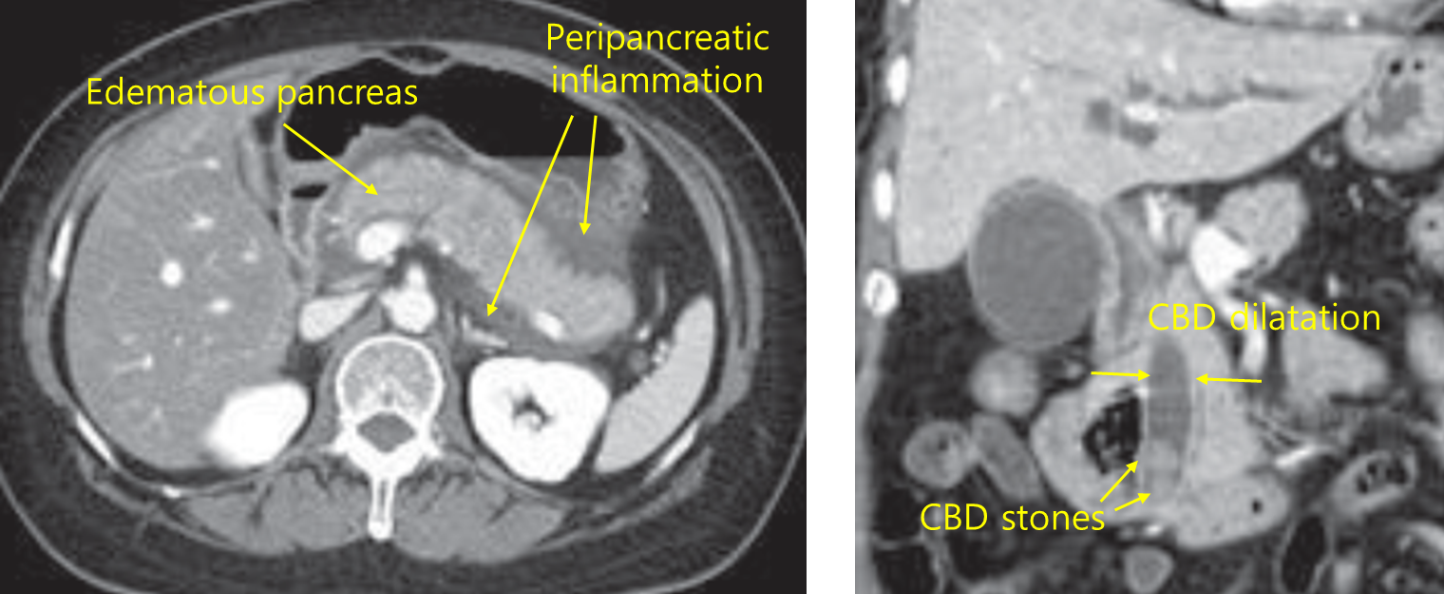

57세 남자가 5시간 전부터 명치가 아프다며 응급실에 왔다. 통증은 등으로 뻗친다고 하며 몸을 구부리면 조금 나아진다고 한다. 1년 전 쓸개돌이 있다고 들었다고 한다. 음주는 하지 않았다고 한다. 혈압 100/65 mmHg, 맥박 101회/분, 호흡 21회/분, 체온 39.2℃이다. 명치와 윗배에 압통은 있지만 반동압통은 없다. 혈액검사 결과는 다음과 같다. 복부 컴퓨터단층촬영 사진이다. 치료는?

백혈구 12,400/mm3, 혈색소 11.3 g/dL, 혈소판 178,000/mm3, 아스파르테이트아미노전달효소 78 U/L, 알라닌아미노전달효소 62 U/L, 알칼리인산분해효소 413 U/L, 감마글루타밀전달효소 597 U/L, 총빌리루빈 5.6 mg/dL, 직접빌리루빈 4.3 mg/dL, 아밀라아제 850 U/L, 리파아제 1,570 U/L, 혈액요소질소 20 mg/dL, 크레아티닌 1.01 mg/dL

Img | CT: 담관 내 담석, 담관 확장, 췌장 종대, 췌장 주위 fluid collection |

1년 전 쓸개돌 진단을 받은 환자로, 몸을 구부리면 완화되는 명치 통증, 등으로 뻗치는 방사통, 혈액검사 상 amylase와 lipase의 상승으로부터 담석에 의한 급성 췌장염을 의심할 수 있다. 백혈구 상승, 발열 등 담관염의 소견도 확인된다. CT 상에서 담석 및 담관 확장, 췌장 종대 및 불명확한 경계가 확인되므로, 급성 췌장염 진단 하에 담석 제거를 위한 내시경역행쓸개이자조영술(ERCP)을 시행하여야 한다.

진단 | • US: 담석, 담관확장 확인 • CT: 췌장 실질의 edema, 췌장 근처 조직의 inflammation |